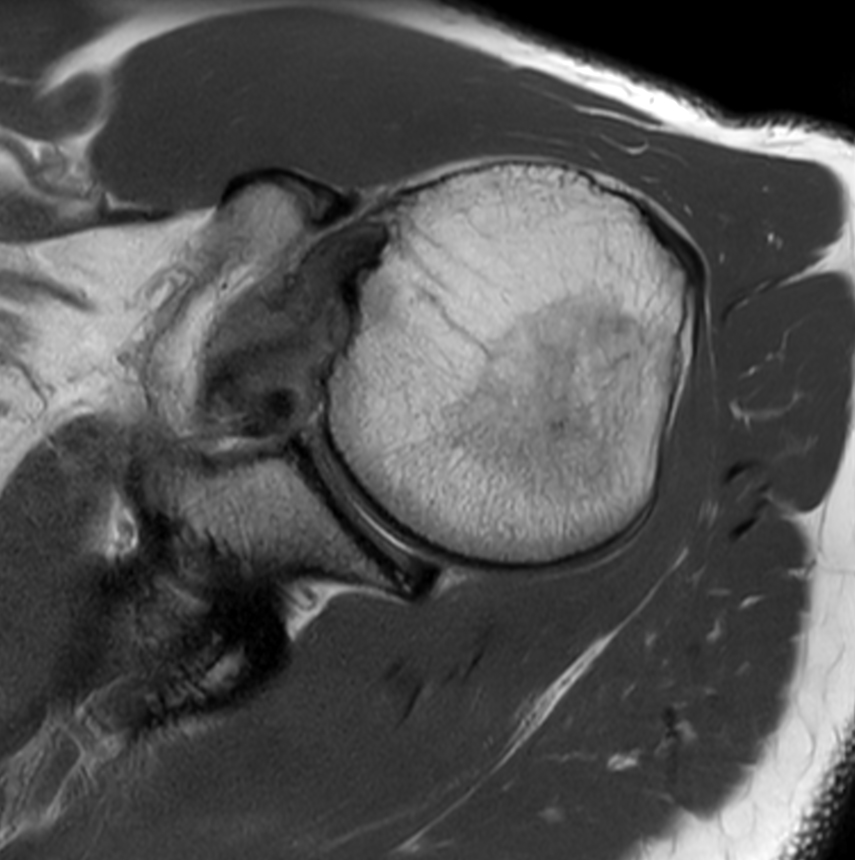

Coronal T2 Mri Shoulder . Well, actually there is thickening of the inferior glenohumeral ligament suggesting multidirectional instability but it is still a good. Do not exceed a 45°. Kept current by radiologists and technologists. In order to recognize the pathology, it is essential to master normal shoulder mri images, which we will cover in this article. This paper will review mri techniques for evaluating the shoulder, normal. Plan the coronal slices on the axial plane and angle the positioning block parallel to the supraspinatus tendon. Normal shoulder mri for reference. Ligaments, cartilage and fluid produce high signal (white); These are blood vessels that should not be misinterpreted for tears. 7 rows mri msk adult shoulder protocol for adult patients. Bone marrow produces a low signal (black).

Coronal T2 Mri Shoulder Normal shoulder mri for reference. Plan the coronal slices on the axial plane and angle the positioning block parallel to the supraspinatus tendon. This paper will review mri techniques for evaluating the shoulder, normal. In order to recognize the pathology, it is essential to master normal shoulder mri images, which we will cover in this article. Do not exceed a 45°. Kept current by radiologists and technologists. 7 rows mri msk adult shoulder protocol for adult patients. Normal shoulder mri for reference. Bone marrow produces a low signal (black). Ligaments, cartilage and fluid produce high signal (white); Well, actually there is thickening of the inferior glenohumeral ligament suggesting multidirectional instability but it is still a good. These are blood vessels that should not be misinterpreted for tears.

MRI shoulder anatomy shoulder coronal anatomy free cross sectional Coronal T2 Mri Shoulder Bone marrow produces a low signal (black). This paper will review mri techniques for evaluating the shoulder, normal. Do not exceed a 45°. Plan the coronal slices on the axial plane and angle the positioning block parallel to the supraspinatus tendon. In order to recognize the pathology, it is essential to master normal shoulder mri images, which we will cover. Coronal T2 Mri Shoulder.